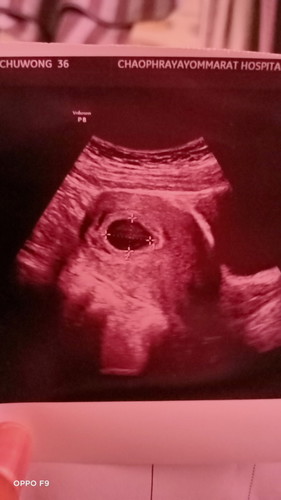

ตั้งครรภ์9week

ไปซาวมาวันนี้เห็นแต่ถุงตั้งครรภ์ไม่เจอตัวน้อง กังวลมากค่ะ ตั้งครรภ์ได้9week

หมอนัดซาวอีกทีวันที่16 ตค. จะมาอัพเดทนะคะ ✌️✌️